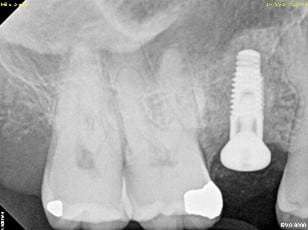

An internal sinus lift is drilled into the membrane when drilling the implant site called an osteotome (usually used to place one or two implants). The internal sinus lift (see yellow arrows) is a more conservative approach used mainly with simultaneous implant placement.

An example of an internal sinus lift can be seen below:

Stage 1: Hopelessly Fractured Tooth

Stage 2: Tooth Extracted, Bone Graft Placed

Stage 3: Implant Placed with a Sinus Lift at the Top